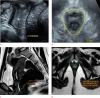

Purpose: The purpose of this study was to investigate magnetic resonance imaging (MRI) and 3-dimensional transperineal ultrasound (3D-TPUS) features of pelvic floor dysfunction (PFD) in symptomatic women in correlation with digital palpation and to define cut-offs for hiatal dimensions predictive of muscle dysfunction.

Methods: This prospective study included 73 women with symptoms suggesting PFD. 3D-TPUS, MRI, and digital palpation of the levator ani muscle were performed in all patients. Levator hiatal antero-posterior (LHap) diameter and area (LH area) were measured at rest and at maximum muscle contraction.

Results: The reduction in LHap diameter and LH area during contraction was significantly less in women with underactive pelvic floor muscle contraction (UpfmC) than in those who had normal pelvic floor muscle contraction by digital palpation (P<0.001). Statistically significant positive correlations (P<0.001) were found between the Modified Oxford Score and 3D-TPUS and MRI regarding the reduction in the LHap diameter (r=0.80 and r=0.82, respectively) and LH area (r=0.60 and r=0.70, respectively). A reduction in LHap of <6.5% on 3D-TPUS and <7.6% on MRI predicted UpfmC with sensitivities of 46.2% and 82.7%, respectively. A reduction in LH area of <3.4% on 3D-TPUS and <3.8% on MRI predicted UpfmC with sensitivities of 75.0% and 88.5%, respectively. MRI was more sensitive in detecting levator avulsion (63.4%) than 3D-TPUS (27.1%).